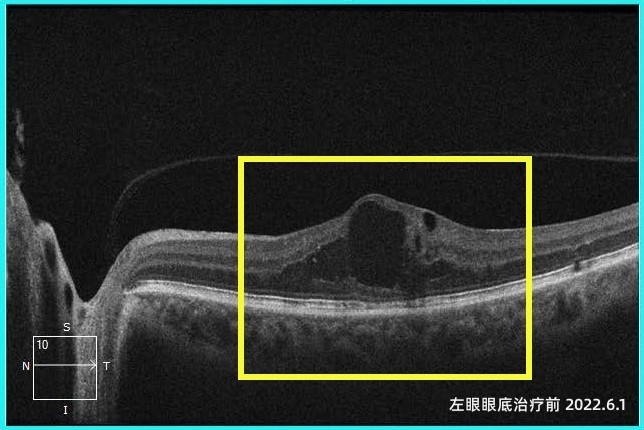

该患者是一位印度教师。四年前左眼视力持续下降,虽然辗转国内外多家医院,却没有很好地得到治疗。后经朋友介绍,慕名来到天津普瑞眼科医院就诊,经系统检查及会诊,眼底病专科李岩院长、李刚主任团队诊断患者为2型左眼黄斑旁毛细血管扩张症( MacTel Ⅱ),这种疾病会导致黄斑中心凹旁毛细血管扩张、微血管瘤形成、血管通透性增加,进而出现黄斑区水肿,严重影响中心视力。经过仔细规划,专家组为患者制定了抗VEGF联合视网膜激光光凝的治疗方案。在连续而系统的诊疗以及不间断的随访后,患者左眼黄斑水肿已经完全消退并长期处于稳定状态。

在眼底病治疗的过程中,患者双眼的白内障问题也日益突出,严重影响了日常生活。天津普瑞眼科医院白内障专科孙堂胜院长团队经过充分评估后,分阶段为其实施了双眼白内障超声乳化联合人工晶体植入术。术后患者双眼视力获得明显提升,对手术效果表示高度满意。在最近一次复查中,患者视力从2022年患病之初时的0.25,提升到如今的0.8。即将告别中国教师生涯时,她表达了对天津普瑞眼科医护技团队的感谢和对未来美好生活的向往,这份跨越山海的国际友情将长久延续下去。